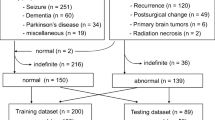

Figure 2 shows a flowchart of study inclusion. During the period above, a total of 2415 PET/CT scans were acquired and 1878 of these were determined to have no abnormal findings. Seven duplicates of scans from the same subjects were excluded so that all scans were from unique subjects. That is, if the same subject had multiple PET/CT scans during the period, only the first one within the period was used. We used all 1878 normal scans for the training of our model (1374 from males and 504 from females; mean age, 58.1 years; age range, 40–90 years). We also used the scans with one or more abnormal FDG foci in the chest region for the evaluation of our method. This evaluation dataset consists of 34 scans from unique subjects (21 from males and 13 from females; mean age, 64.4 years; age range, 41–89 years) and includes both 28 pulmonary and 17 extrapulmonary abnormal FDG uptake foci. Further details of the lesions in this dataset are shown in Table 1. A board-certified radiologist (N.H., 15 years of experience in PET/CT interpretation) annotated the locations of all the uptake foci voxel-wise.